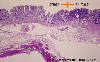

조기위암 IIc형(IIc+I)

X선 화상상으로는 융기성분이 눈에 띈 IIc+I형 조기위암(---다지점 합동 소화관 텔레이미지 컨퍼런스 증례---증례제시:이바라키현, 이바라키현립 중앙병원・지역암센터)

마이크로

병리학 분류

악성 상피성종양/선암